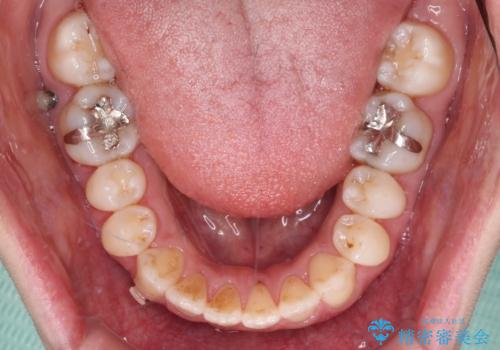

- 受け口傾向でクロスバイトの前歯を治したいとのことで来院された患者様です。

下顎骨が若干左側に変位していたため、右側にアンカースクリューを使用し、積極的に移動させながらインビザラインにて矯正治療を行うこととしました。